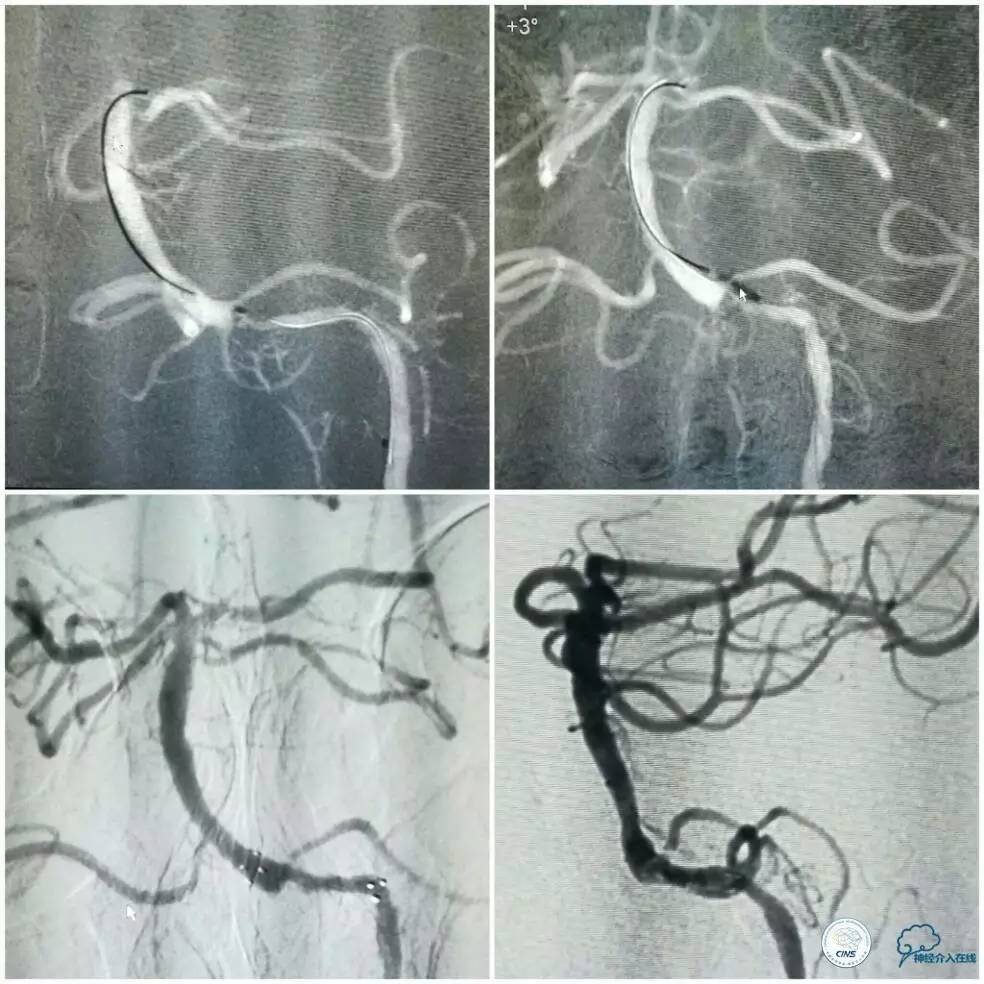

治疗中最大困难如术前估计是微导丝过病变困难,原因是病变狭窄程度重,且成角(斑块偏心因素加重病变成角)。在将微导丝(Traxcess,0.014")头端塑了一个小弯后,微导丝艰难通过病变(图8)。

图8

微导丝到位后,原想跟进微导管(Echelon 10)行微导管造影证实在真腔,但因微导管无法越过病变而作罢。将微导丝后接Dockling延长导丝后撤出微管,依次送入Gateway1.5 mm x 9 mm,2.0 mm x 9 mm球囊预扩后,放置Winspan 3.5 mm x 15 mm支架(图9)。术后前向血流明显改善,残余狭窄约15%(图9)。

图9